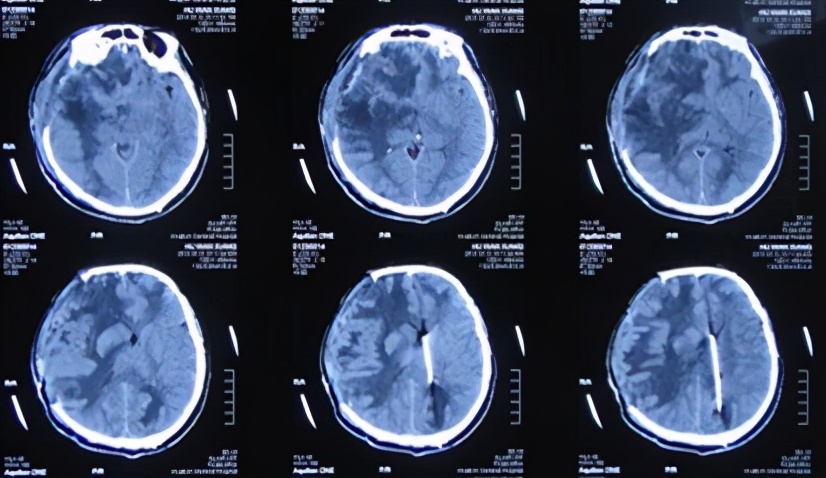

患者于2013年9月17日凌晨因车祸致头部外伤、昏迷,急诊于山东省聊城市某医院就诊,头CT检查发现双额及右颞叶多发脑挫裂伤并右侧脑室受压、中线左移(图-1),当天进行了右侧额颞叶脑挫裂伤血肿清除并去骨瓣减压术,术后头CT:去骨瓣减压术后状态(图-2)。

图-1:2013年9月17日术前头CT

图-2:2013年9月17日术后头CT

术后,患者减压窗张力持续偏高,并于2013年9月20日即开颅术后第3天,切口出现渗液红肿,给予抗感染及切口换药处理,并行切口分泌物细菌培养(注:2天后报告为阴沟肠杆菌生长)。于开颅术后第4天和第5天即2013年9月21日和9月22日两次行腰椎穿刺,均提示脑脊液压力升高明显。开颅术后第8天即2013年9月25日,行头CT检查:脑膜脑膨出较前加重(图-3),而且这期间头部切口感染仍进行性恶化,且体温升高至39℃以上、颈部僵硬,意识障碍逐渐加重等表现。

图-3:2013年9月25日头CT

于2013年9月29日即开颅术后第12天(转院后第4天),转至北京某著名的某三甲医院,入院当日行头CT检查:脑膨出及脑肿胀均严重(图-4)。

图-4:2013年9月29日头CT